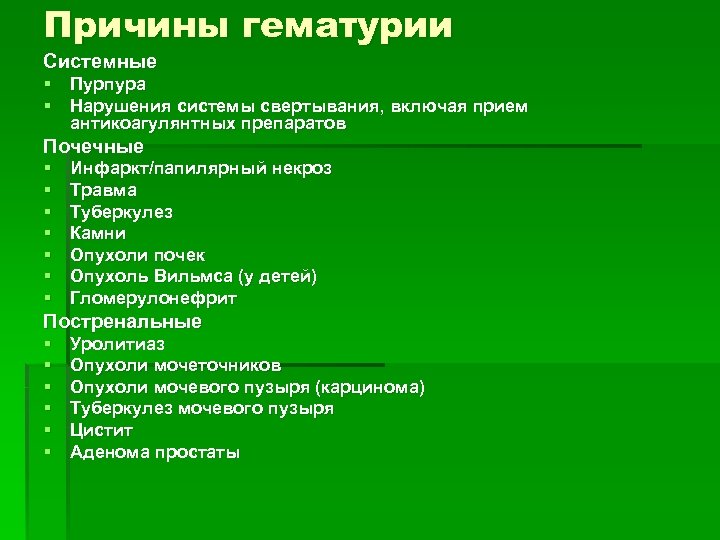

Причины гематурии Системные § Пурпура § Нарушения системы свертывания, включая прием антикоагулянтных препаратов Почечные § § § § Инфаркт/папилярный некроз Tравма Tуберкулез Камни Опухоли почек Опухоль Вильмса (у детей) Гломерулонефрит Постренальные § § § Уролитиаз Опухоли мочеточников Опухоли мочевого пузыря (карцинома) Туберкулез мочевого пузыря Цистит Аденома простаты